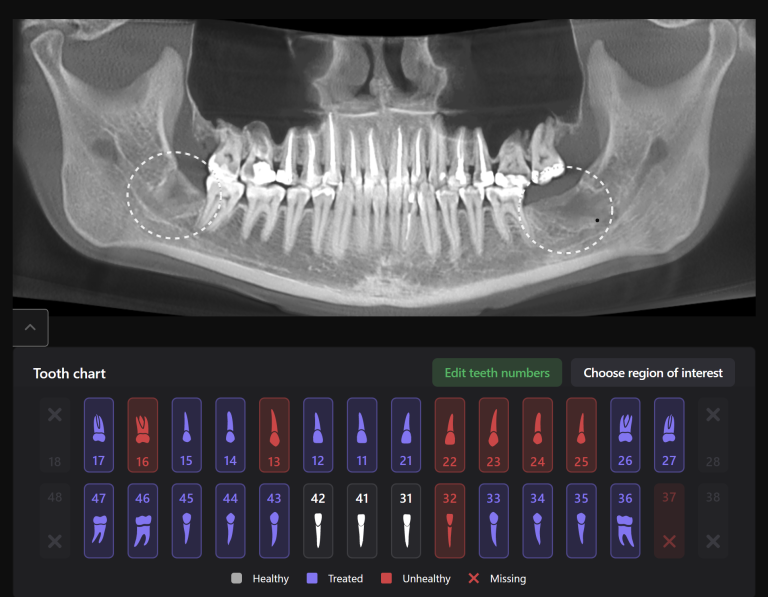

Panoramic reconstruction from CBCT